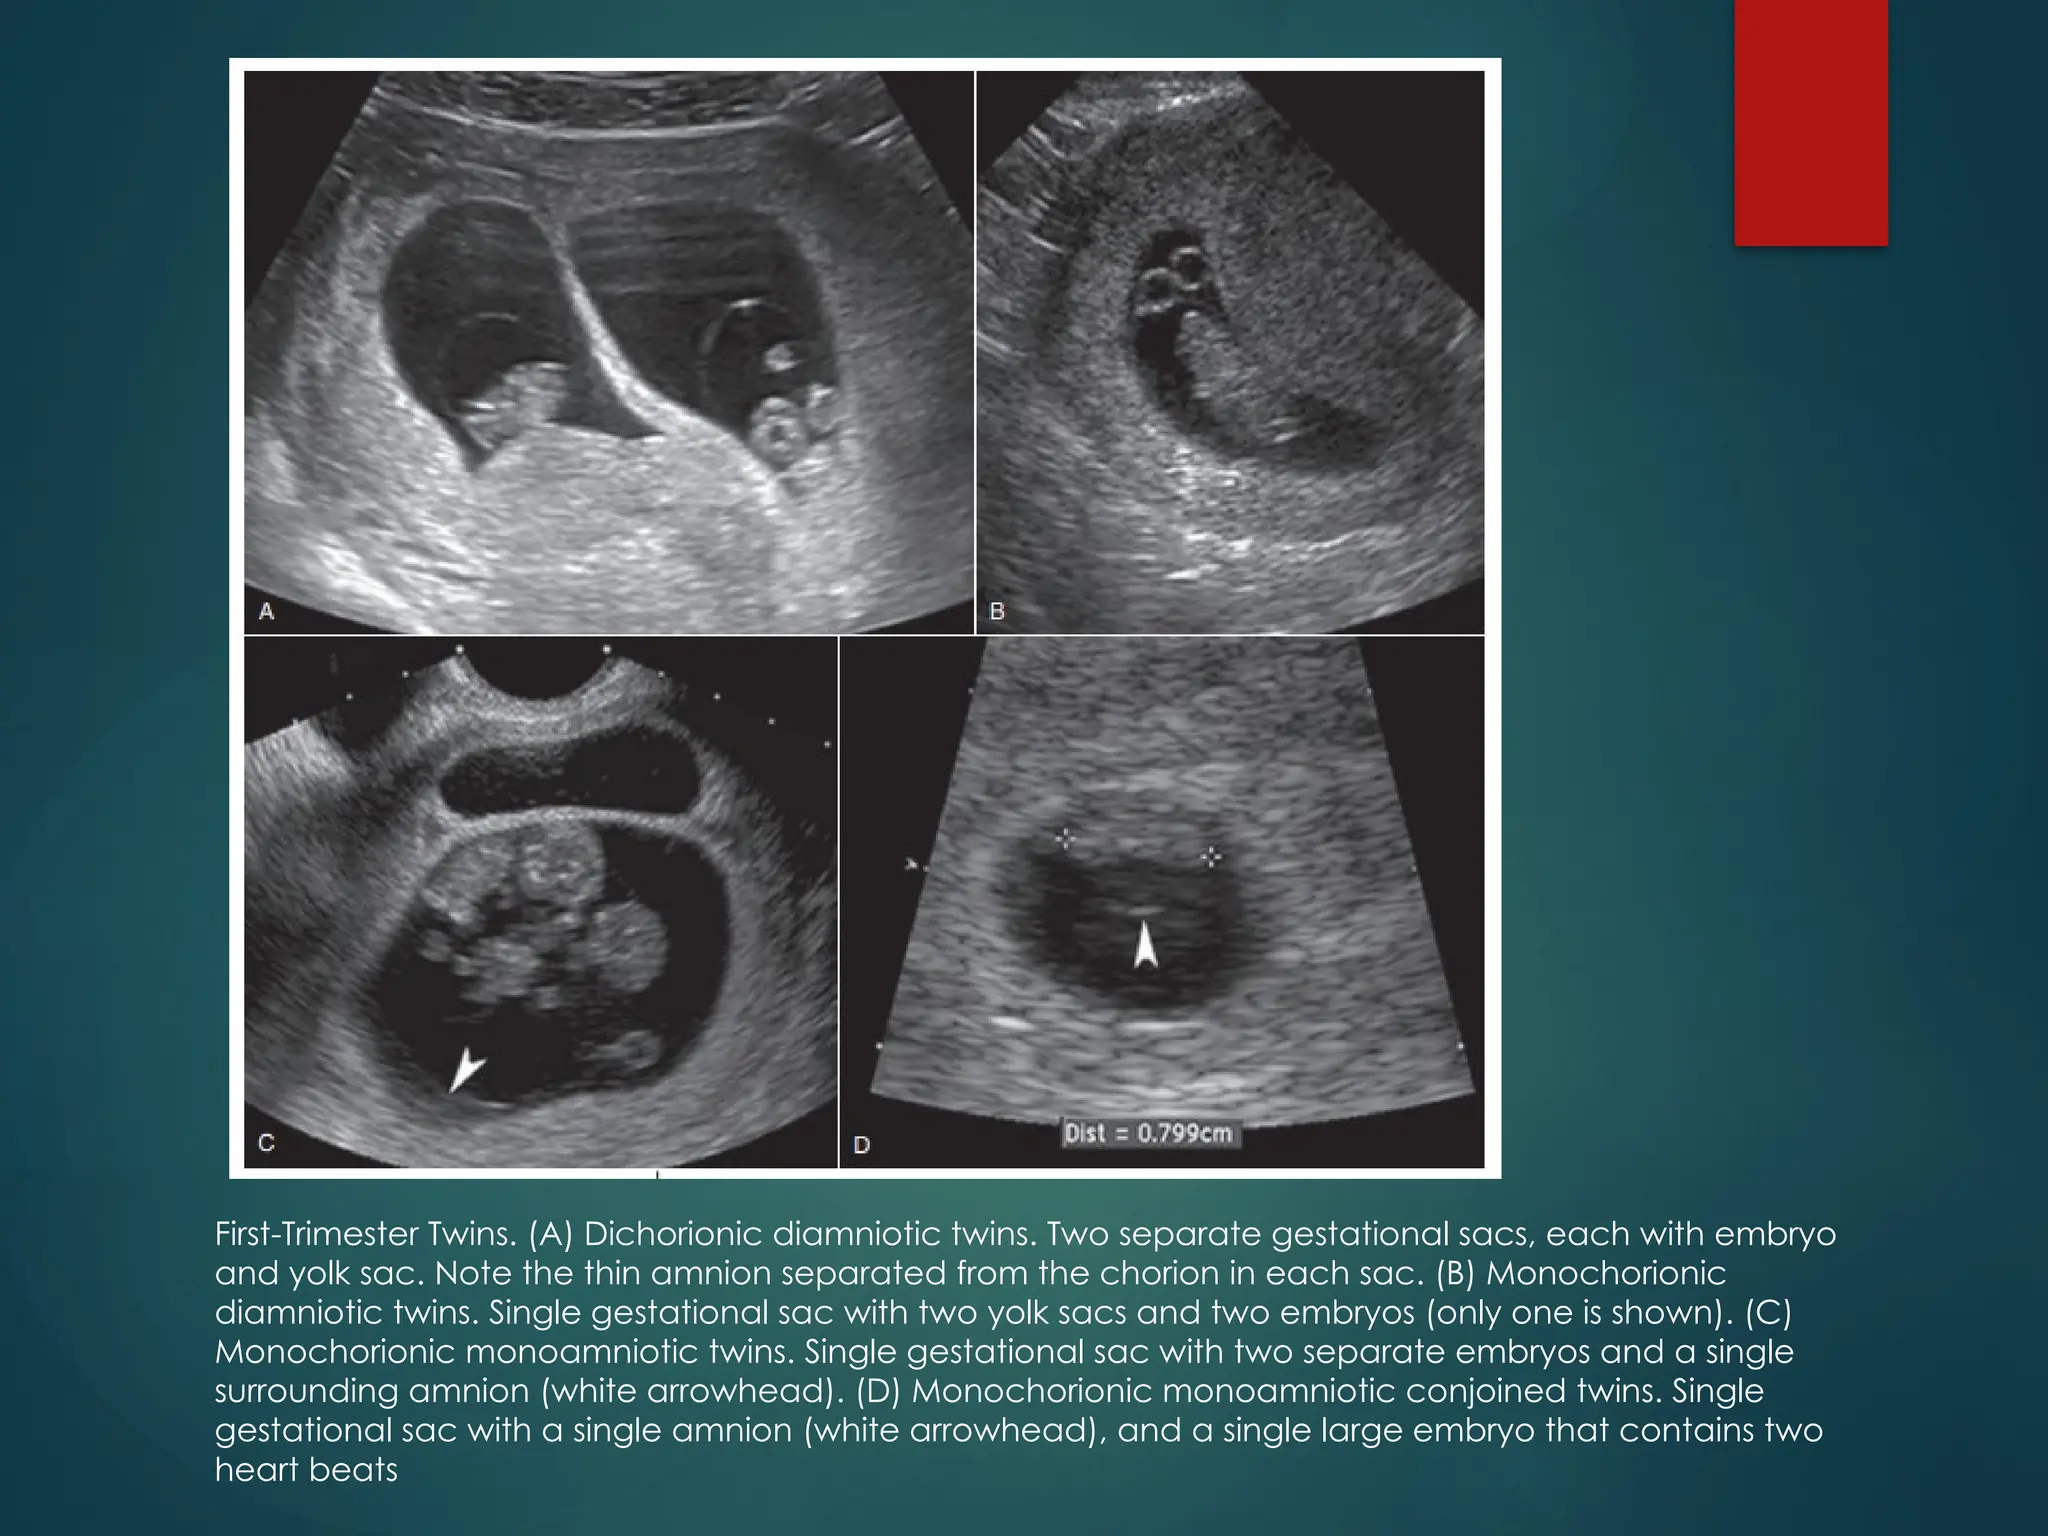

First-Trimester Twins. (A) Dichorionic diamniotic twins. Two separate gestational sacs, each with embryo

and yolk sac. Note the thin amnion separated from the chorion in each sac. (B) Monochorionic

diamniotic twins. Single gestational sac with two yolk sacs and two embryos (only one is shown). (C)

Monochorionic monoamniotic twins. Single gestational sac with two separate embryos and a single

surrounding amnion (white arrowhead). (D) Monochorionic monoamniotic conjoined twins. Single

gestational sac with a single amnion (white arrowhead), and a single large embryo that contains two

heart beats

First-Trimester Twins. (A)Dichorionic diamniotic twins. Two separate gestational sacs, each with embryo and yolk sac. Note the thin amnion separated from the chorion in each sac. (B) Monochorionic diamniotic twins. Single gestational sac with two yolk sacs and two embryos (only one is shown). (C) Monochorionic monoamniotic twins. Single gestational sac with two separate embryos and a single surrounding amnion (white arrowhead). (D) Monochorionic monoamniotic conjoined twins. Single gestational sac with a single amnion (white arrowhead), and a single large embryo that contains two heart beats